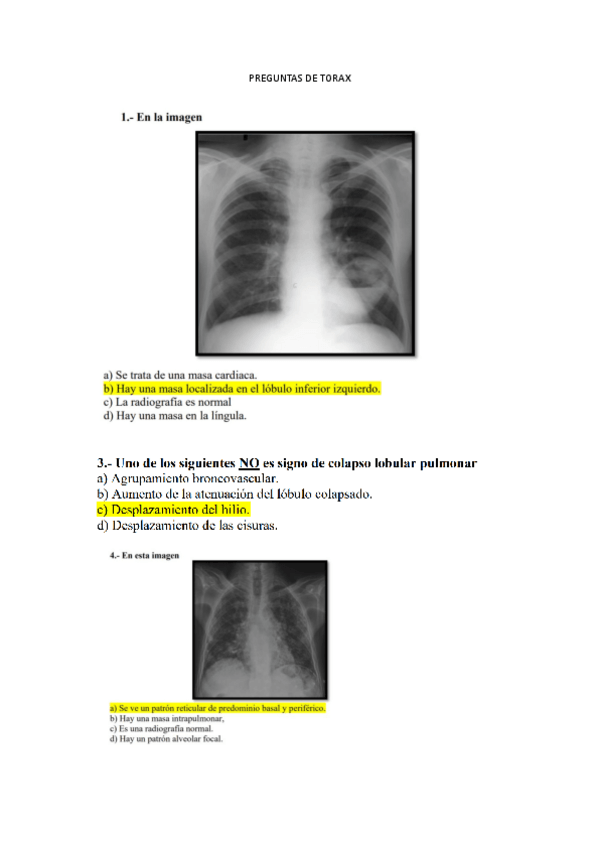

preguntas-torax.pdf